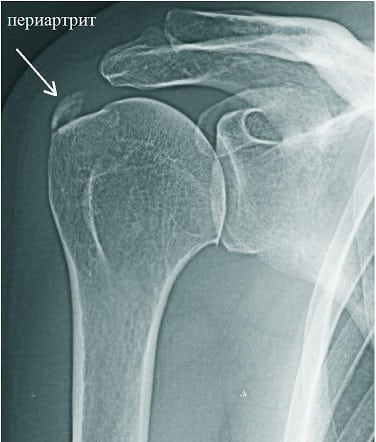

Ультразвуковая диагностика наиболее информативна при обнаружении плечелопаточного периартрита на ранних стадиях. А с помощью рентгенографии определяются изменения,возникшие при хронической прогрессирующей патологии. Для поздней стадии характерно отложение мельчайших кристаллов кальция. При анкилозирующем периартрите на рентгенологических снимках хорошо просматриваются сращение суставной щели и наличие признаков остеопороза (изменения плотности костных тканей) головки кости плеча. Артроскопическое обследование внутренней поверхности сустава проводится только при необходимости, так как оно сопряжено с повышенной вероятностью осложнений.